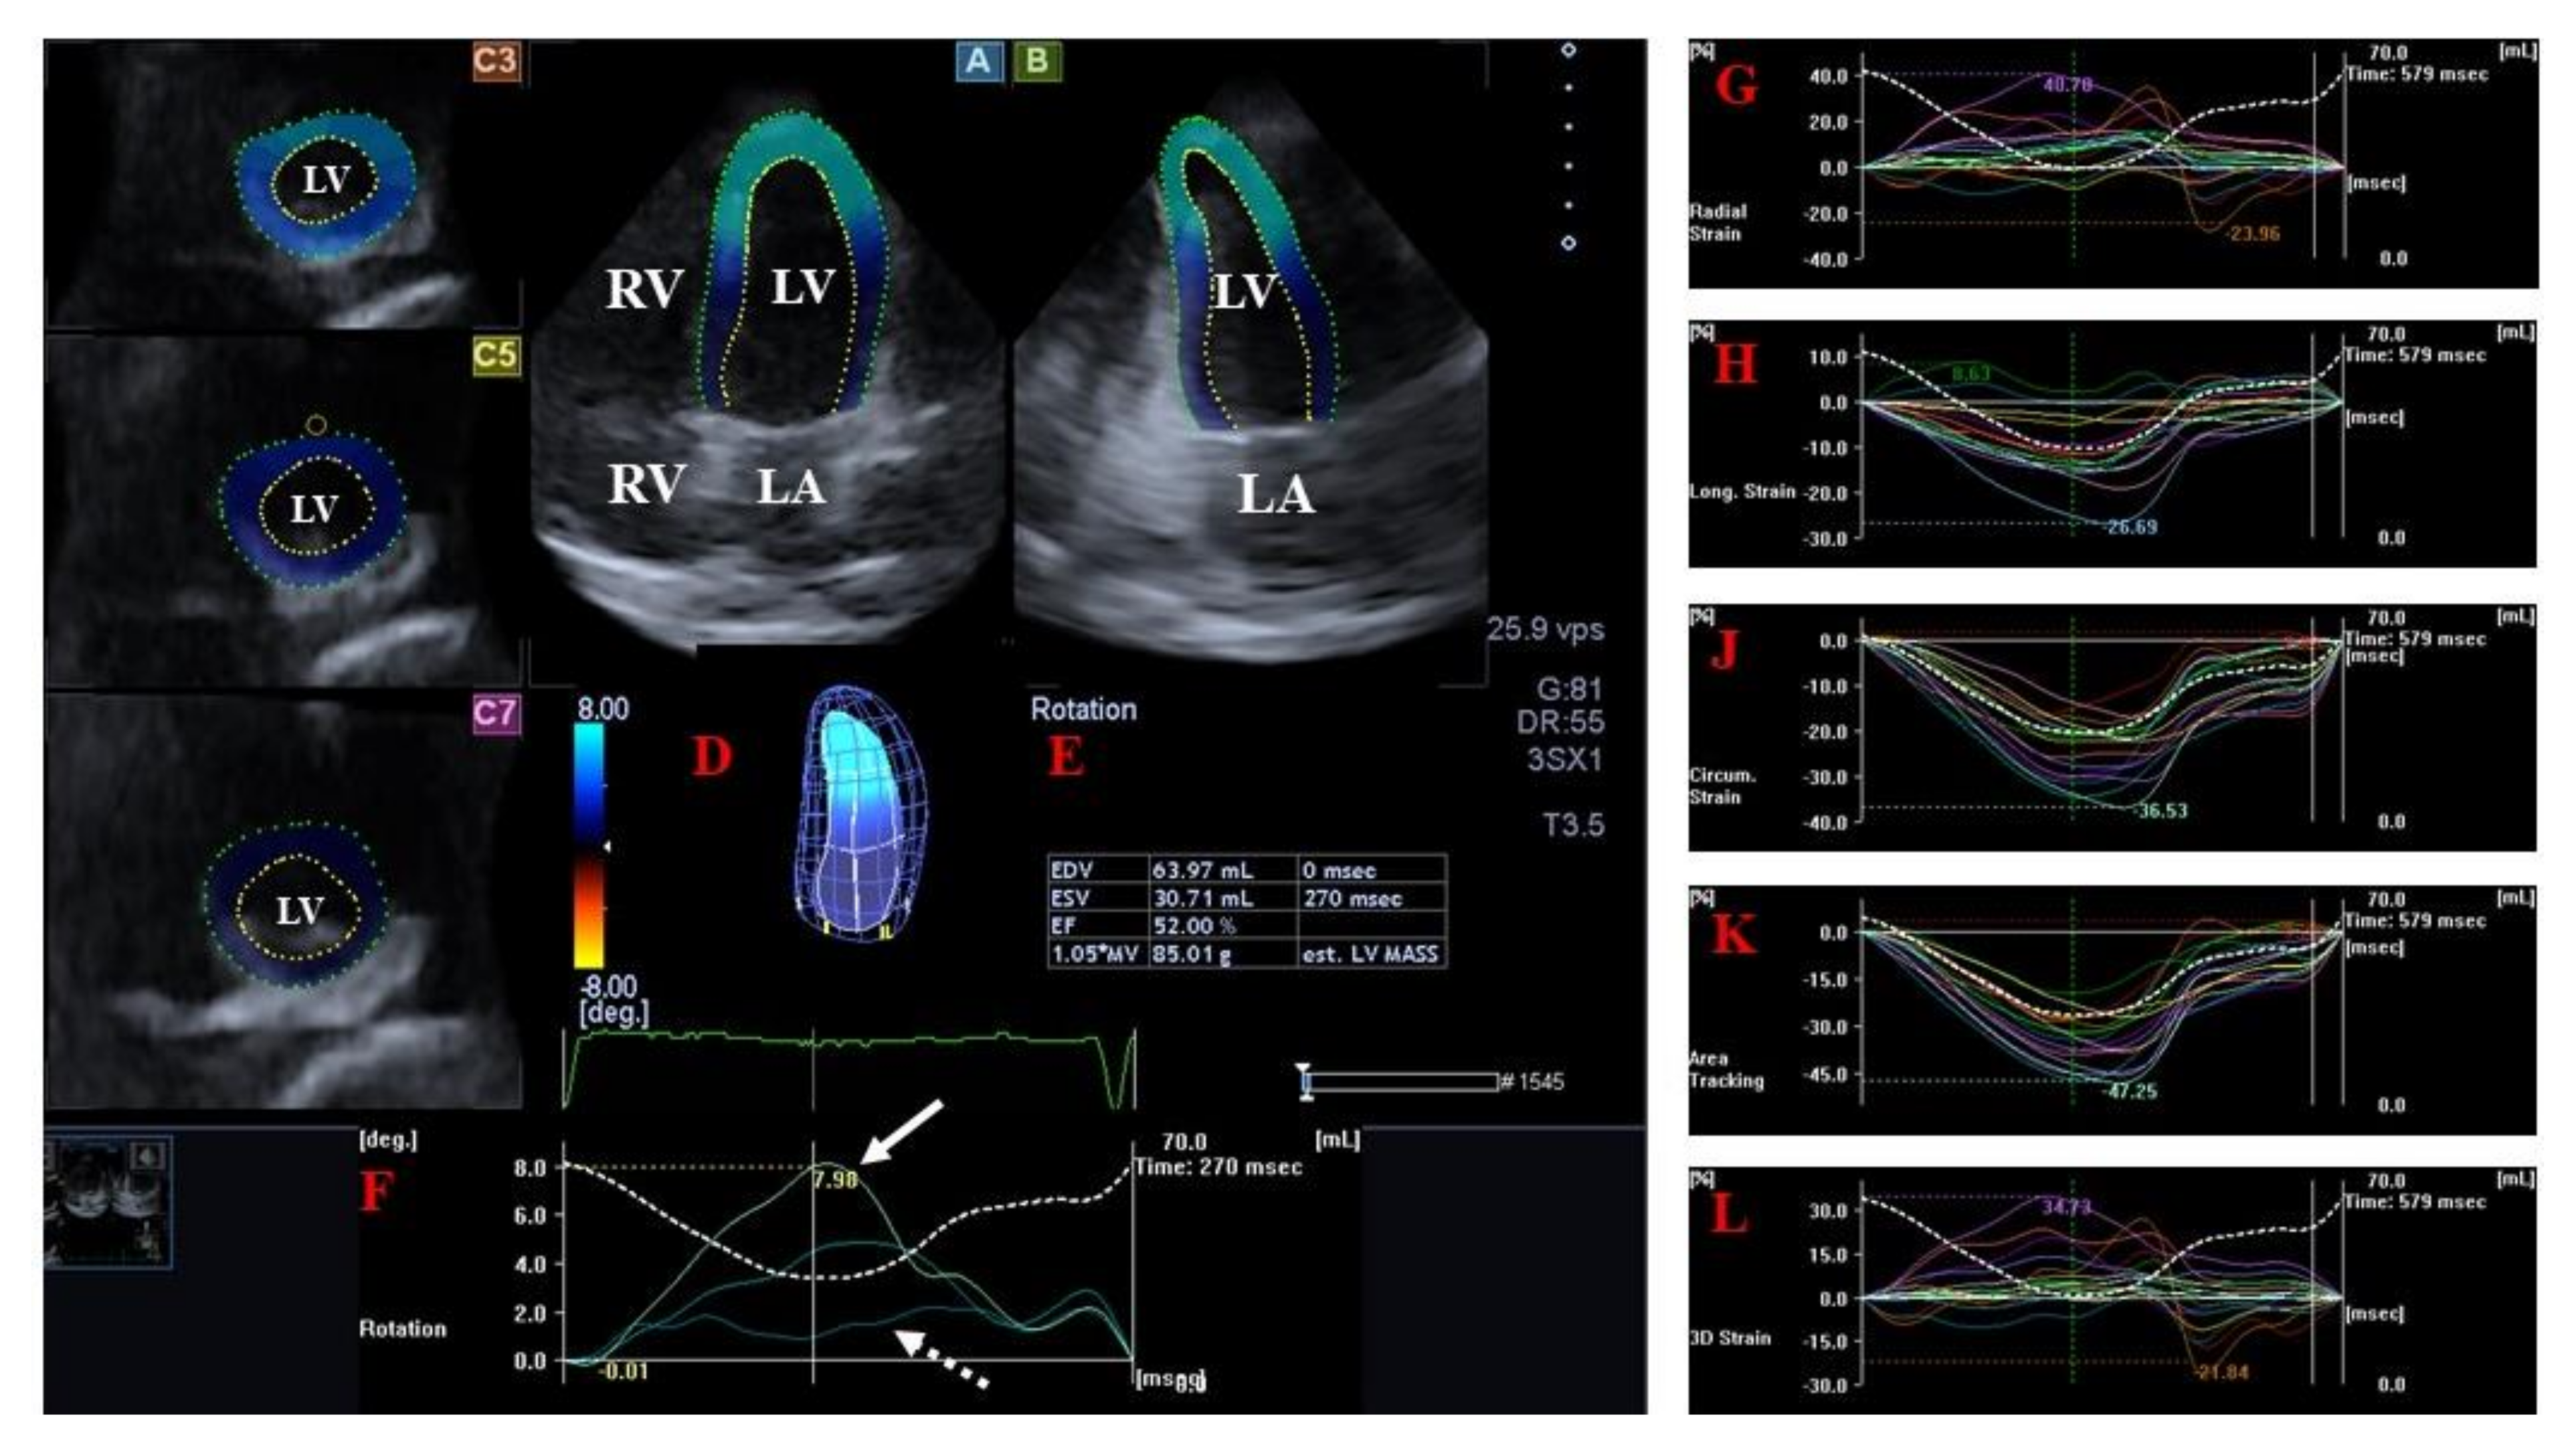

3.1. Left Ventricle

LV Strains and Rotational Parameters

- Kormányos, Á.; Domsik, P.; Kalapos, A.; Orosz, A.; Lengyel, C.; Valkusz, Z.; Trencsányi, A.; Forster, T.; Nemes, A. Left ventricular twist is impaired in acromegaly: Insights from the three-dimensional speckle tracking echocardiographic MAGYAR-Path Study. J. Clin. Ultrasound 2018, 46, 122–128. [Google Scholar] [CrossRef]

- Nemes, A.; Kormányos, Á.; Domsik, P.; Kalapos, A.; Gyenes, N.; Lengyel, C.; Valkusz, Z. Diabetes mellitus deteriorates left ventricular deformation in acromegaly-analysis from the three-dimensional speckle-tracking echocardiographic MAGYAR-Path Study. Quant. Imaging Med. Surg. 2021, 11, 410–414. [Google Scholar] [CrossRef]

- Gyenes, N.; Kormányos, Á.; Vágvölgyi, A.; Valkusz, Z.; Balogh, L.; Papp, G.; Lengyel, C.; Nemes, A. Left ventricular deformation: Similarities and dissimilarities in elite sport activity- and acromegaly-related abnormalities. Results from the three-dimensional speckle-tracking echocardiographic MAGYAR-Sport and MAGYAR-Path Studies. Orv. Hetil. 2023, 164, 308–316. [Google Scholar] [CrossRef]

- Nemes, A.; Kormányos, Á.; Domsik, P.; Kalapos, A.; Lengyel, C.; Valkusz, Z.; Forster, T. Left ventricular ‘rigid body rotation’ in a patient with acromegaly (from the MAGYAR-Path Study). Quant. Imaging Med. Surg. 2017, 7, 378–379. [Google Scholar] [CrossRef]

- Kormányos, Á.; Domsik, P.; Kalapos, A.; Gyenes, N.; Valkusz, Z.; Lengyel, C.; Forster, T.; Nemes, A. Active acromegaly is associated with enhanced left ventricular contractility: Results from the three-dimensional speckle-tracking echocardiographic MAGYAR-Path Study. Rev. Port. Cardiol. 2020, 39, 189–196. [Google Scholar] [CrossRef]